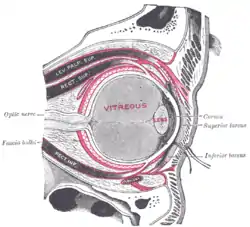

The right eye in sagittal section, showing the fascia bulbi. (Tarsi labeled at right.) | |

The tarsi (SG: tarsus) or tarsal plates are two comparatively thick, elongated plates of dense connective tissue, about 10 mm (0.39 in) in length for the upper eyelid and 5 mm for the lower eyelid; one is found in each eyelid, and contributes to its form and support. They are located directly above the lid margins.[1] The tarsus has a lower and upper part making up the palpebrae.

Along the inner margin of the tarsus are modified sebaceous glands known as tarsal glands (or meibomian glands), aligned vertically within the tarsi: 30 to 40 glands in the upper lid, and 20 to 30 in the lower lid, which secrete a lipid-rich product which helps keep the lacrimal secretions or tears from evaporating too quickly, thus keeping the eye moist.[2]